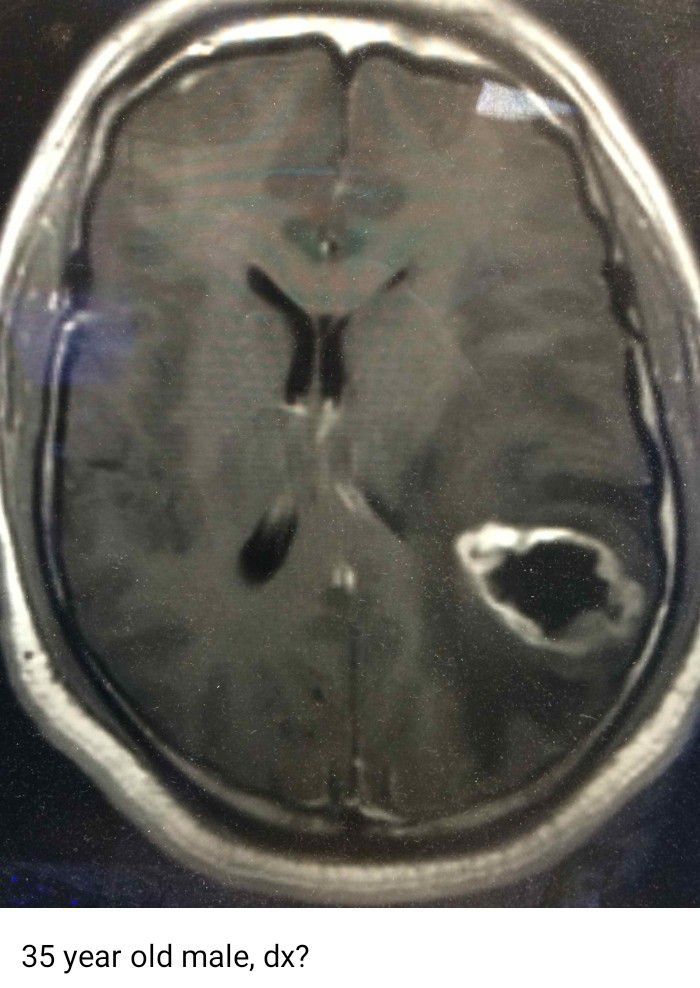

Dr Meredith Grey

Neurosurgery

Neurosurgeon